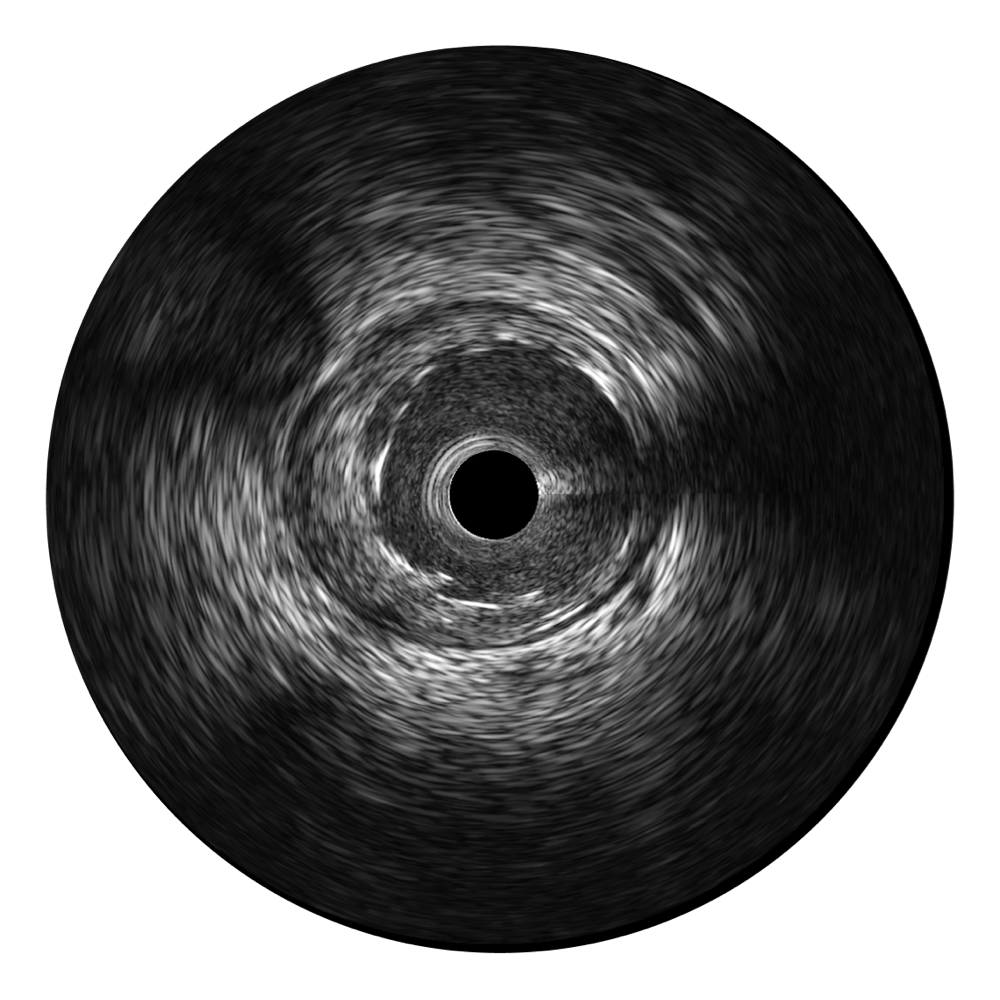

• DB中国旗舰官方网站宽频IVUS图像

• 传统IVUS图像

对比传统IVUS导管成像,DB中国旗舰官方网站宽频IVUS图像的近场支架梁显影更细腻,远场中膜外血管仍清晰可辨,兼顾远中近,兼顾分辨力与穿透深度